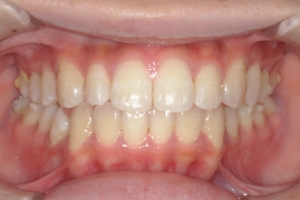

AFTER

治療後

下の前歯が上あごの歯ぐきに当たるほど噛み合わせが深く、そのことが原因で上顎歯列の正中にすき間(正中離開)が生じていました。部分矯正ですき間を無理やり閉じても、噛み合わせが深いままでは治療後の再発リスクが高くなります。そのため全体矯正で奥歯の噛み合わせを整え、噛み合わせを浅くしつつ前歯を並べました。正中離開は戻りやすい傾向があるので、再発を防ぐため固定式リテーナーを推奨しています。